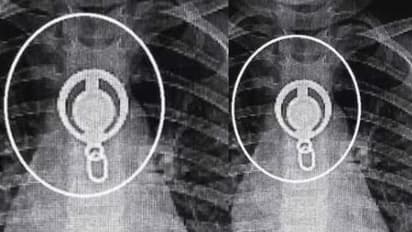

വലുപ്പമേറിയ ലോക്കറ്റ് വിഴുങ്ങിയതോടെ കുട്ടിക്ക് ശ്വാസമെടുക്കാനടക്കം ബുദ്ധിമുട്ടായി. ഇതോടെയാണ് വീട്ടുകാർ വിവരമറിയുന്നത്. കുട്ടി അസ്വസ്ഥത പ്രകടിപ്പച്ചതോടെ സ്വകാര്യ ആശുപത്രിയിൽ എത്തിച്ച് എക്സ് റേ എടുത്തു. അപ്പോഴാണ് അന്നനാളത്തിൽ ലോക്കറ്റ് കുടുങ്ങിയതായി സ്ഥിരീകരിച്ചത്. പ്രാഥമിക ശുശ്രൂഷ നൽകിയ കുട്ടിയെ ഉടൻതന്നെ പാലാ ചേർപ്പുങ്കലിലെ സ്വകാര്യ ആശുപത്രിയിൽ എത്തിച്ചു.

ഡോക്ടർമാരെത്തി ലോക്കറ്റെടുക്കാൻ ശ്രമിച്ചെങ്കിലും സാധിച്ചല്ല. തുടർന്ന് പുലർച്ചെയോടെ ശസ്ത്രക്രിയ കൂടാതെ ലോക്കറ്റ് പുറത്തെടുത്തു. കുട്ടിക്ക് മറ്റ് ആരോഗ്യപ്രശ്നങ്ങളൊന്നുമില്ലെന്നും സുഖം പ്രാപിച്ച കുട്ടി ആശുപത്രി വിട്ടെന്നും അധികൃതർ അറിയിച്ചു.